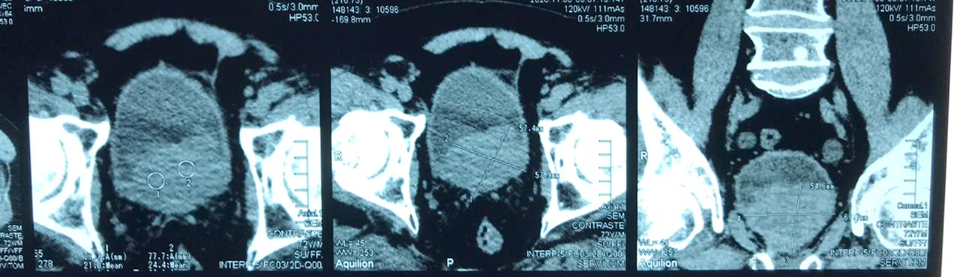

- creat 6,12, Uréia 186

- PSA = 4,76

- USG – dilatação bilateral, massa vesical

Recidiva de neoplasia de próstata ??

Neoplasia de Bexiga ??